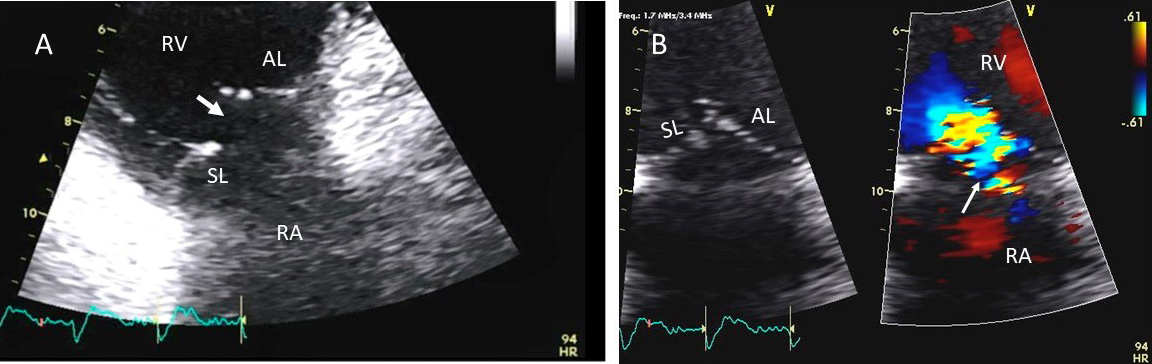

Fig. 6.Tricuspid regurgitation induced by pacemaker lead valve perforation. (A) Transthoracic 2D 4 chamber view showing pacemaker lead going through the TV leaflet (white arrow) and causing TR. (B) 3D enface view of the TV from the right atrial perspective showing the pacemaker lead going through the margin of the septal leaflet (SL) of the TV (white arrow). (C) 3D color Doppler view of the TV from the atrial perspective showing origin of TR at the site of leaflet perforation. MV, mitral valve; AV, aortic valve; PL, posterior leaflet; AL, anterior leaflet

Fig. 7.Tricuspid regurgitation following endomyocardial biopsy. (A) Flail tricuspid valve leaflet that occurred as a complication of an endomyocardial biopsy. Apical 4 chamber view showed flail septal leaflet (SL, septal leaflet; AL, anterior leaflet). (B) Color-flow Doppler imaging. Eccentric, anteriorly directed jet of tricuspid regurgitation (SL, septal leaflet of tricuspid valve; AL, anterior leaflet of tricuspid valve).